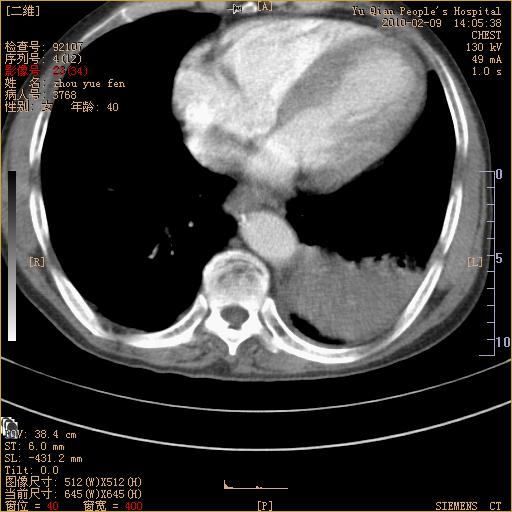

男性,73岁,咳嗽咳血数天,诊为肺ca伴左肺下叶后段阻塞性炎症、肺不张妥否?

右下肺有转移?

左下肺中央型肺癌伴结段形肺不张,左侧胸腔积液,纵隔内见部分增大淋巴结(反应性增生或转移)

左下基底干支气管明显变窄。

左肺下叶基底段支气管狭窄,左肺门增大,左肺下叶团片状病灶。中心型肺癌伴柱塞性炎症可能大,建议支气管镜检查。

左下肺中央型肺癌伴节段性肺不张,左侧胸腔积液,纵隔内见肿大淋巴结

左下基底段支气管变窄。建议进一步纤支镜检查。

1、左肺下叶后基地段肺癌伴阻塞性炎症,左下肺门淋巴结转移。2、左侧胸腔积液。